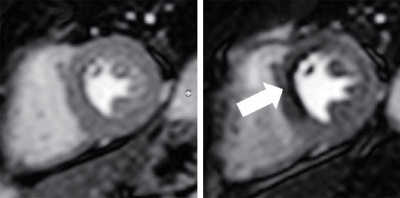

Abb. 1

CT Koronarangiographie: Computertomographischer Nachweis einer hochgradigen Verengung im Bereich eines Koronargefässes (weisser Pfeil) in 3D.